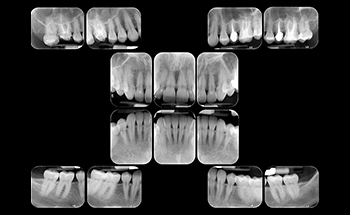

A radiografia é um exame essencial para a Odontologia. Suas inúmeras técnicas permitem a observação de objetos dentários e patologias distintas. Uma das técnicas mais usadas pelos profissionais é a radiografia interproximal, que proporciona uma visualização nítida de dentes posteriores. RADIOGRAFIA PERIAPICAL DIGITAL Esta técnica possibilita uma visão em conjunto dos elementos dentais e dos tecidos ósseos adjacentes. Utilizada principalmente para avaliação óssea do periápice dental, podendo ser utilizada também para pesquisa de cárie, sua extensão e comprometimento pulpar, avaliação do nível da crista óssea alveolar e tipo de reabsorção, conhecimento da forma anatômica, número de raízes e condutos radiculares. O que é radiografia interproximal? Também chamada de bite-wing, a radiografia interproximal é uma técnica radiográfica intraoral em que você obtém imagens das faces mesial, distal e das coroas dos pré-molares e molares, além das cristas ósseas vizinhas do maxilar e da mandíbula. Resumindo, permitem a visualização mais nítida dos dentes posteriores. O termo “bite-wing” significa “asa de mordida” — termo da Odontologia que se refere à forma como o paciente segura o receptor de raios-X (entre os dentes). Como a radiografia interproximal é realizada? Para conseguir a radiografia interproximal, o profissional de Radiologia posiciona o aparelho para que o feixe de raio-X atinja as faces proximais perpendicularmente e paralelamente ao plano oclusal. A angulação horizontal é orientada paralelamente às faces proximais dos dentes que se deseja radiografar. Já a vertical varia de 8 a 10º positivos. No processo tradicional, a asa de mordida é feita em um receptor com filme radiográfico nas dimensões 3 x 4 cm ou 3,4 x 2,2 cm. É feita numa película normal com aleta de cartolina ou colocada em posicionador interproximal. O filme é posicionado intraoralmente e o paciente faz a contenção ocluindo sobre a aleta. Caso o odontologista queira estudar as cristas alveolares, recomenda-se colocar o filme em pé. Para que o odontologista consiga visualizar os dentes superiores e inferiores em um mesmo exame, a radiografia interproximal é dividida em quatro: duas para a região dos dentes molares e duas para os dentes pré-molares. Já na versão digital, não há necessidade de filme. O profissional faz o posicionamento correto do aparelho e conta apenas com o auxílio do posicionador para que o paciente faça a oclusão. O sistema de placas de fósforo, responsável por receber a imagem, faz com que a taxa de exposição à radiação seja 70% menor do que a emitida por uma radiografia convencional. posição da cabeça: PSM perpendicular ao solo e linha do trago à asa do nariz paralela ao assoalho; arcada: o exame deve mostrar a face distal dos 2º pré-molares e a face distal dos caninos. O exame é totalmente indolor e não causa desconforto ao paciente. Em menos de 2 minutos, o profissional obtém a imagem que necessita. Obviamente, se o odontologista necessitar de mais zonas anatômicas, o tempo tenderá a aumentar. A radiografia interproximal é simples, pode ser feita tanto em crianças quanto em adultos e não requer preparação prévia. Gestantes podem fazer radiografia interproximal? O ideal é que gestantes evitem exames de raio-X durante a gravidez. No entanto, a radiografia interproximal não apresenta contra indicações significativas. Para evitar qualquer tipo de problema, a paciente deve avisar tanto ao odontologista quanto ao profissional de Radiologia sobre o atual tempo de gravidez. Mesmo que a gestação não seja confirmada, é essencial avisar sobre a suspeita. Nesse caso, o profissional vai tomar o mesmo cuidado que tomaria com uma gestante: o uso de um avental de chumbo para proteger o feto da exposição à radiação. Quais as indicações da radiografia interproximal? Confira os casos em que a radiografia interproximal é indicada: visualização das coroas dos dentes superiores e inferiores numa mesma imagem; relação entre dentes decíduos e germes dos permanentes; visualização de possíveis mudanças na cavidade pulpar; visualização de cáries oclusais e interproximais; identificação de excessos marginais; avaliação do estado periodontal; visualização de cálculos dentais; visualização das cristas ósseas; visualização de perdas ósseas; pesquisa de cálculo gengival; reincidência de cáries; pode ser usada para avaliar a eficácia de alguns tratamentos, como as restaurações. Quais as vantagens da radiografia interproximal? a radiografia interproximal oferece maiores resolução e nitidez, pois atende aos 5 itens da radiografia ideal com mais qualidade que outras técnicas; ideal para análise de presença de cáries oclusais e interproximais, que são mais difíceis de diagnosticar durante um exame clínico, além de trauma oclusal; é mais rápida e simples, portanto exige menos exposição do paciente aos raios-X. A versão digital da radiografia interproximal proporciona ainda mais benefícios: imagens digitais economizam armazenamento e são mais fáceis de compartilhar entre outros profissionais; permitem marcações e edições de contraste, brilho e tamanho; promovem a sustentabilidade, já que a receptação de imagens não lida com substâncias tóxicas tanto ao ambiente quanto aos profissionais e pacientes; equipamentos de radiologia digital não geram resíduos poluentes ao meio ambiente; exigem menos exposição aos raios-X; raramente necessitam de retrabalho. Afinal, por mais que seja um exame relativamente simples, ele proporciona a visualização de alterações e patologias de difícil detecção em um exame clínico convencional. Valor sob consulta Central de Atendimento – (21) 3273-2379 Whatsapp – (21) 96408-7396 🕑 Exame realizado por ordem de chegada. Favor chegar 1h antes do final do expediente. 💻 Com exceção do modelo em gesso, todos os exames são compatíveis para entrega digital.